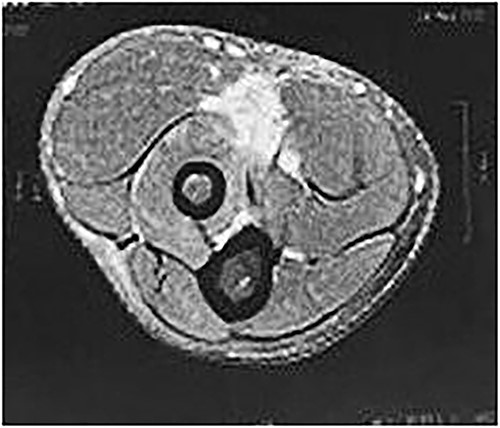

On physical examination (Fig. 1), the patient exhibited a visible deformity of the arm (inverted Popeye sign), a positive Hook test for distal biceps injury, symmetric elbow flexion strength, slightly decreased supination strength with pain, but with a complete range of motion for passive and active pronation-supination and flexion-extension. Ultrasonography and magnetic resonance imaging revealed a complete rupture of the distal biceps tendon (Figs 2–4).

Axial MRI image showing absence of the biceps tendon in the region of the radial tuberosity and edema in the area.